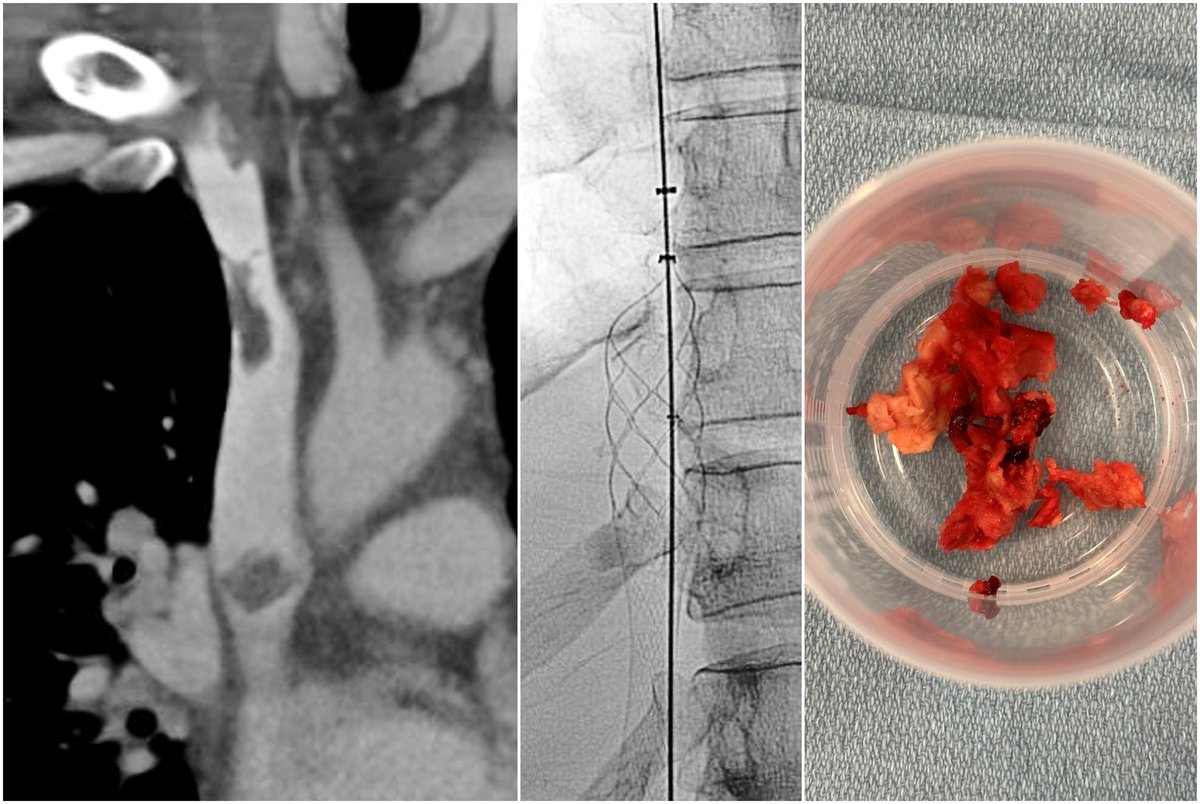

Venous stent dysfunction, including thrombosis, may occur in 62% of the patients previously treated with stent reconstruction at 5 years. Aspiration thrombectomy with FlowTriever may represent a single-session technique for restoration of thrombosed venous stents. Inari, now part of Stryker

Endovascular tissue sampling using the ClotTriever thrombectomy system provides useful benign, malignant, and infectious histopathologic information. Inari, now part of Stryker Eric Monroe, MD Matt Abad-Santos David Shin CVIR Journal

Venous thrombectomy allows for the removal infected thrombus, vegetations, and debris and allows for the clearance of persistent bacteremia. Inari, now part of Stryker University of Washington IR Residency UW Radiology SIR RFS SIR ECS Society of Interventional Radiology CIRSE